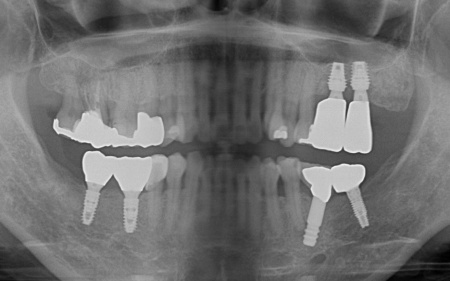

骨吸収の影響で温存が難しい左上奥歯(第1大臼歯、第2大臼歯)と、大きく傾いてしまっている右下の親知らず(第3大臼歯)の3本は抜く必要があることをお伝えしました。

そのうえで、欠損部を補う方法としてインプラント治療を提案し、同意いただきました。

左上については、顎の骨が大きく失われているため、骨を再生させる処置「GBR(骨再生誘導法)」を実施してインプラントを支えるために必要な骨量を確保したうえで、インプラントを埋入する計画を立てました。

次に、右下に装着されているブリッジを除去してから右下の親知らずを抜き、欠損部(第1大臼歯、第2大臼歯の部分)にインプラントを埋入しました。

また、右下の手前にある奥歯2本(第1小臼歯、第2小臼歯)は、新しく詰め物を作製して噛み合わせと見た目を整えています。

最後に、完成した人工歯をインプラントに取り付け、噛み合わせや見た目に問題がないことを確認し、治療を終了しました。